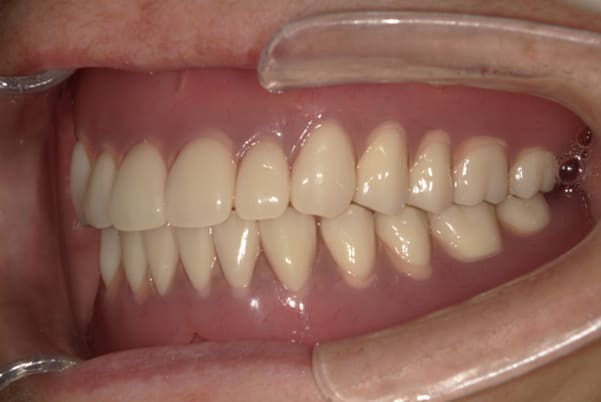

こちらは、口を少し開いた時の治療前と治療後の

口元です。

正面から見た時にクラスプが目立たないように、

歯ぐきになじむ素材にて入れ歯を製作し、痛くなく自然に馴染み快適に生活を送れるようになりました。